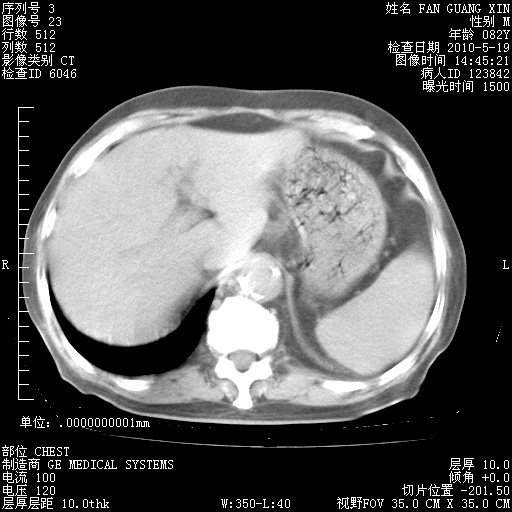

再治疗10天后的肺部CT

再治疗10天后的肺部CT 纵膈窗

阅读此次胸部CT,肺间质渗出性改变较入院时有吸收。目前从体温、白细胞、中性分叶明显增高,肯定存在细菌感染(发生医院感染哦,若无消化道及泌尿系统等感染的依据,肺部感染可能大)。若你院头孢哌酮舒巴坦钠耐药率较高,同意你的方案,若48小时体温仍高,可考虑使用碳青霉稀类抗菌药物,同时可予超声雾化、注意滴数时加大液体量。白蛋白33.30g/L较低哦,需加强营养等支持治疗。

从白细胞总数和中性比例看好像合并感染。肺部纹理好像比上次多,支气管炎?其他感染?